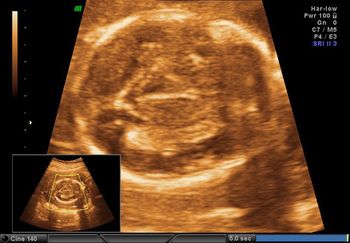

Case History: 25-year-old patient presents for antenatal ultrasound.